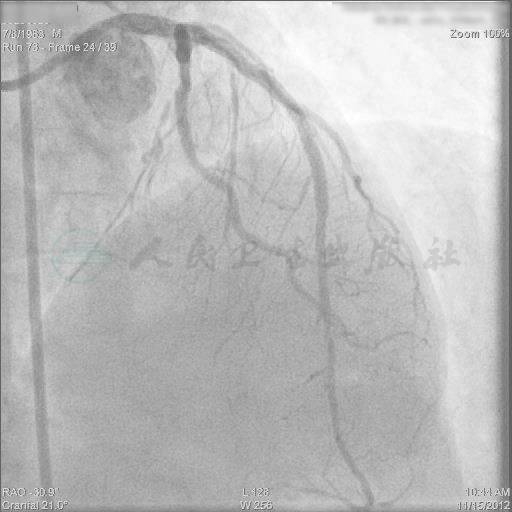

冠状动脉造影结果

左主干远端90%狭窄,前降支开口完全闭塞,无明显残端,回旋支中段80%狭窄,右冠脉无明显狭窄;右冠优势型;右冠脉至前降支侧支循环形成良好,前降支中段存在明显狭窄性病变(图1~图4)。

选择右侧桡动脉及右侧股动脉途径。经右侧桡动脉途径送入6F AL 0.75指引导管至右冠脉开口,经股动脉途径选用6F EBU 3.5指引导管至左冠脉开口,进行双侧冠脉造影了解闭塞段病变的特征(图5)。双侧冠脉造影显示闭塞段长度约15mm左右,闭塞段血管没有明显钙化和扭曲或成角,预测导丝通过闭塞病变可能性大,成功率较高。

图5 双侧冠脉造影显示闭塞段病变特征